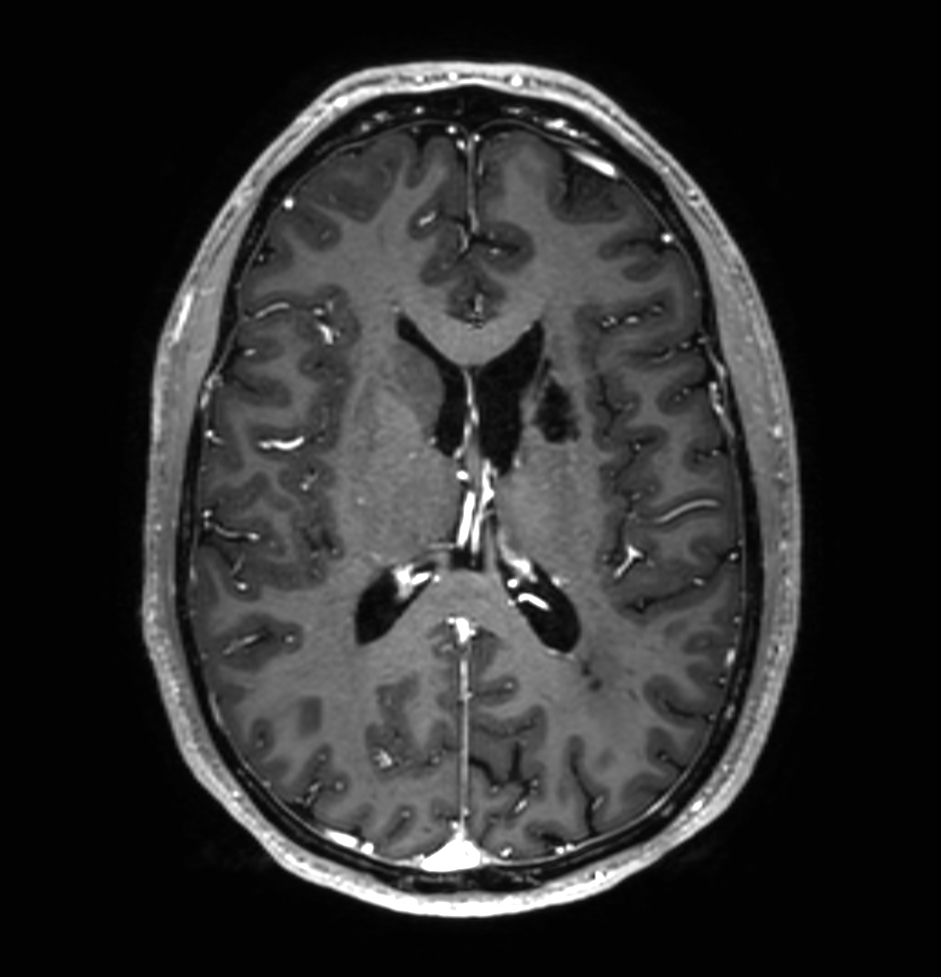

3D T1w TFE (post-gado)